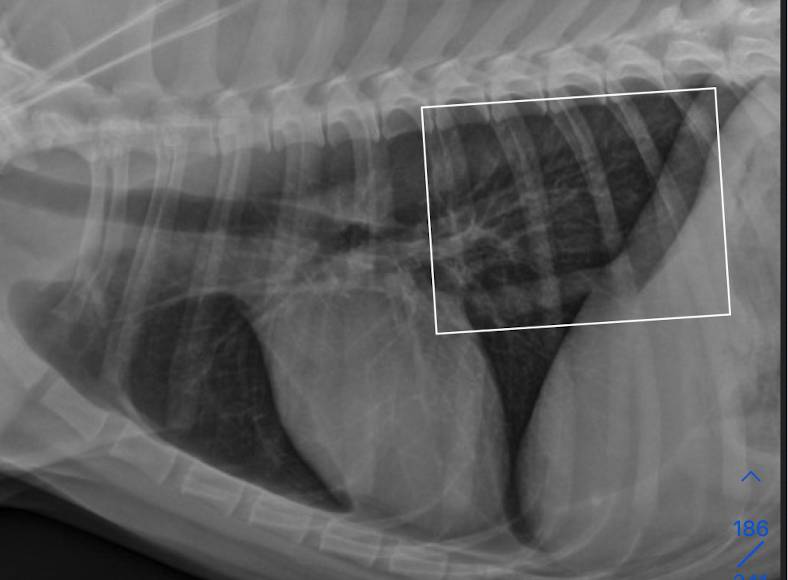

what is this showing

A

left: enlargment of middle tracheobronchial Lymph node → ventral displacement of carina

right: left atrial enlargmentdorsal displacement of carina

both will show bowing of the mainstem bronchi on VD (cowboy) and double opacity sign